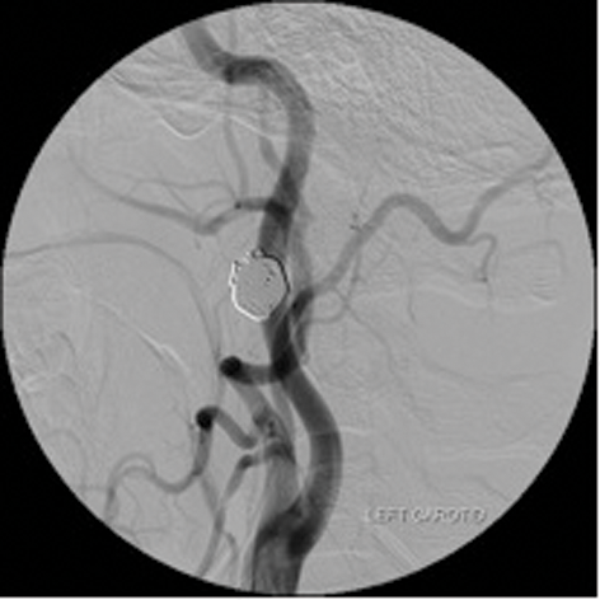

Detachable balloons, particles and / or sclerosants, and stents are used in the endovascular treatment of these lesions. (Figure 3 shows a case of a traumatic external carotid-jugular AV fistula treated by coil embolisation).

Figure 3: ECA- jugular fistula before and after embolisation.